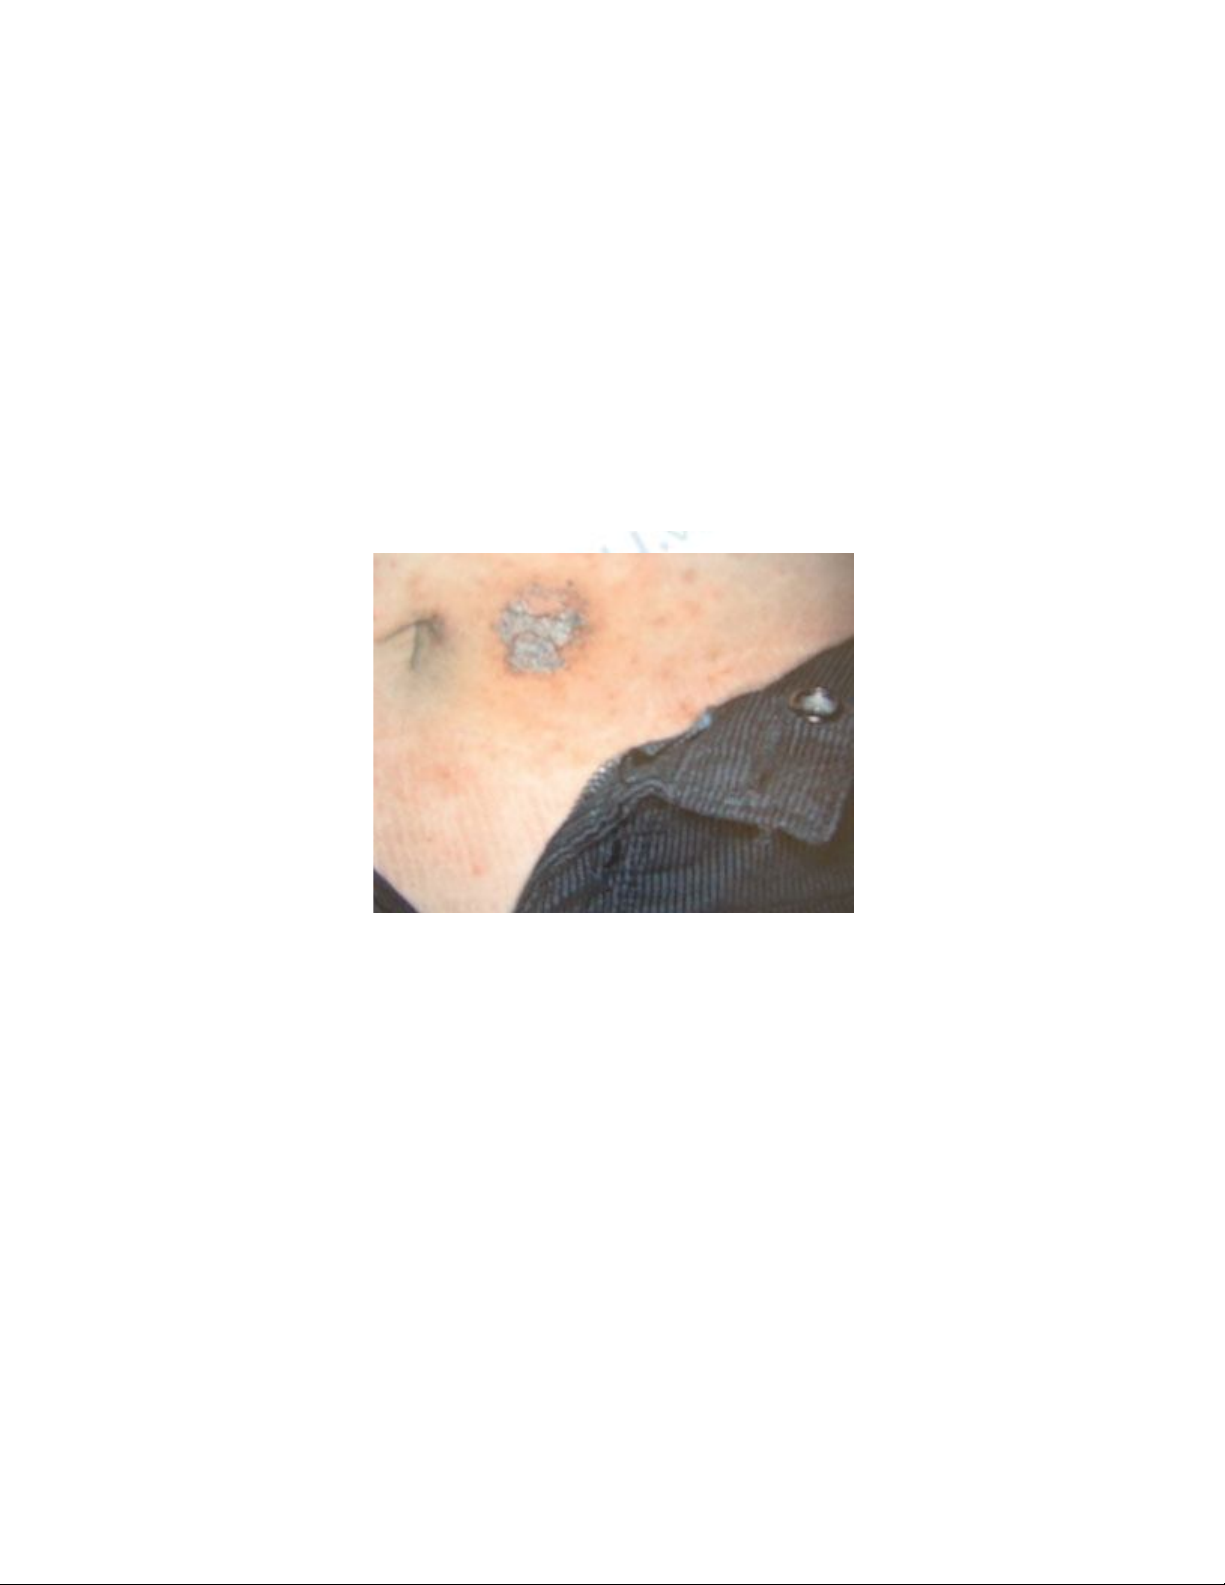

Một trường hợp bị viêm da do tiếp xúc.

Ảnh: K.V .